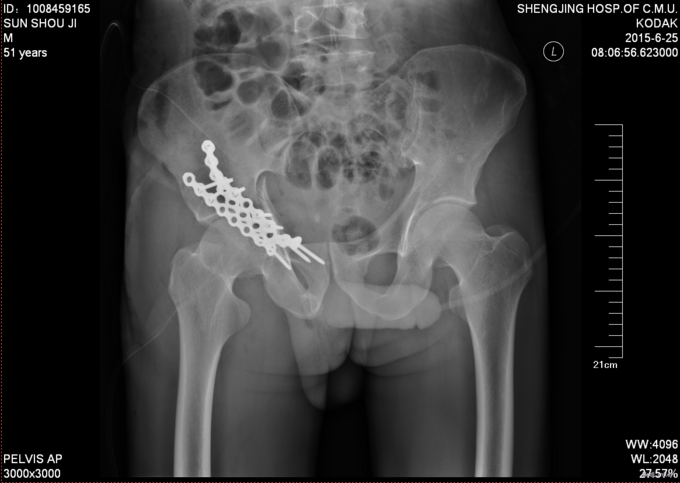

患者入院后急诊行右髋关节脱位手法复位术,右胫骨结节骨骼牵引术。术后患者骨骼牵引约8公斤,术后约一星期后择期行右髋关节骨折切开复位钢板内固定书,术后患者病情平稳,术后三天转入当地医院继续治疗。